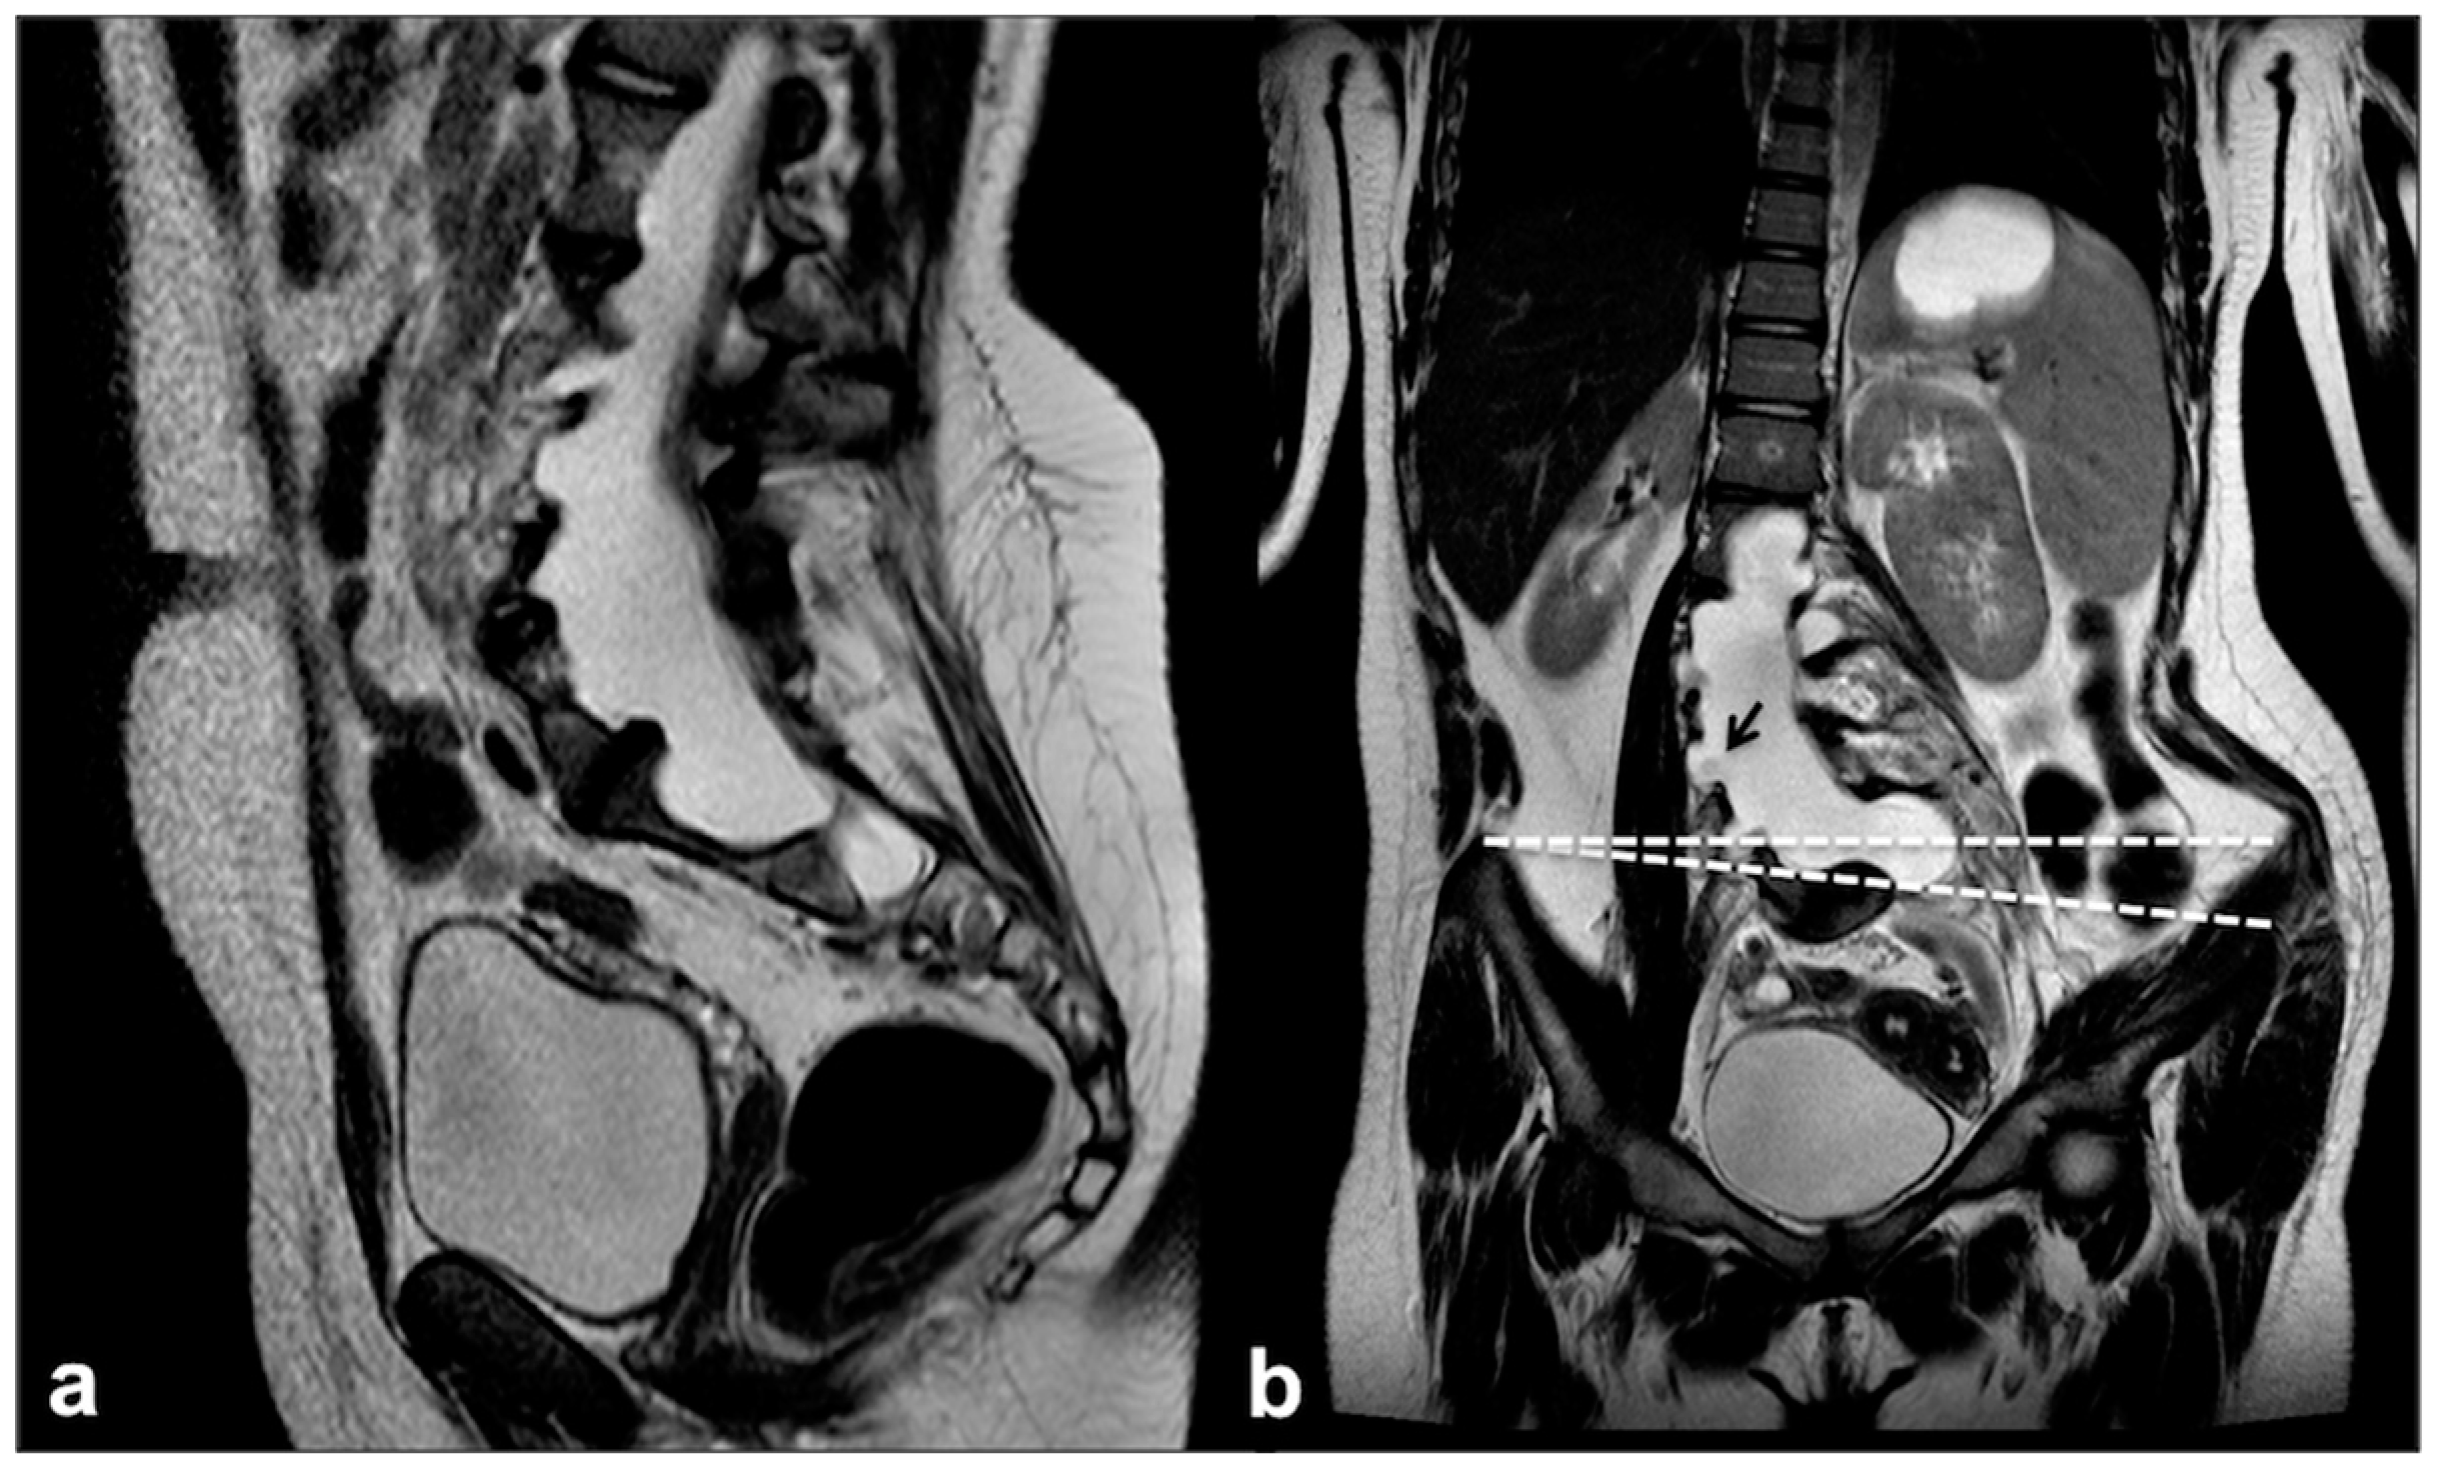

4.2. Dural Ectasia, Meningocele and Spinal Deformity: An Etiopathological Continuum

- Shah, S.; George, K.J. The association of spinal deformity with dural ectasia in neurofibromatosis type 1. Br. J. Neurosurg. 2019, 33, 620–623. [Google Scholar] [CrossRef] [PubMed]

- Derdabi, I.; El Jouadi, H.; Edderai, M. Dural ectasia: A manifestation of type 1 neurofibromatosis. Pan Afr. Med. J. 2018, 31, 226. [Google Scholar] [CrossRef]

- Nguyen, R.; Dombi, E.; Akshintala, S.; Baldwin, A.; Widemann, B.C. Characterization of spinal findings in children and adults with neurofibromatosis type 1 enrolled in a natural history study using magnetic resonance imaging. J. Neuro-Oncol. 2015, 121, 209–215. [Google Scholar] [CrossRef]